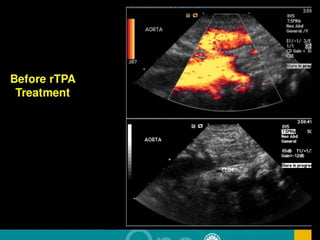

LMWH (Enoxaparin)LMWH (Enoxaparin)

Before LMWH TreatmentBefore LMWH Treatment

After LMWH TreatmentAfter LMWH Treatment